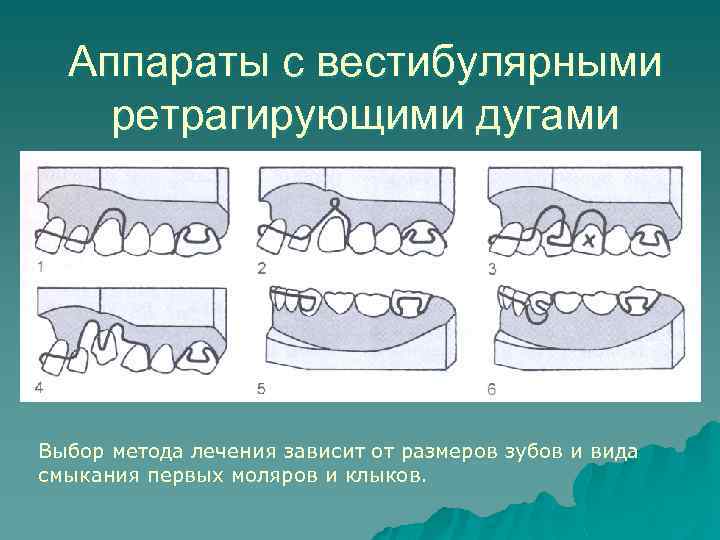

Аппараты с вестибулярными ретрагирующими дугами Выбор метода лечения зависит от размеров зубов и вида смыкания первых моляров и клыков.